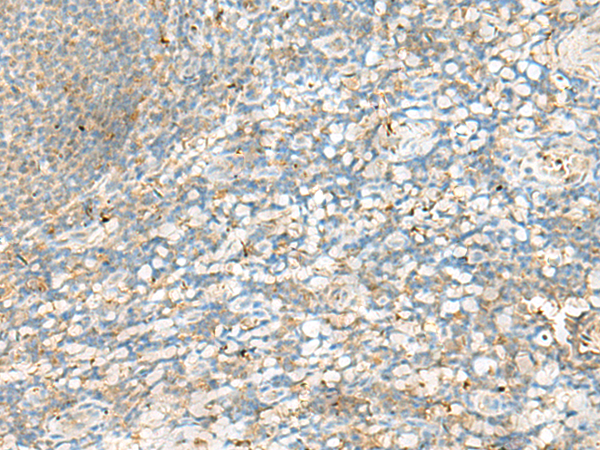

分类: 科研抗体货号: P09879别名: IDDM1; CELIAC1; HLA-DQB应用: IHC反应种属: Human

分类: 科研抗体货号: P09884别名: DR4; DRB4; HLA-DR4B应用: WB,IHC反应种属: Human